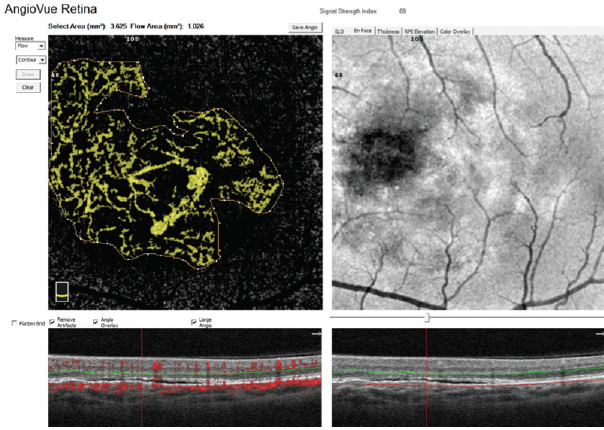

Figure 2. CNV flow area quantification with AngioAnalytics.

A helpful step for everyday clinical applications of OCTA has been the development of AngioAnalytics (Optovue), software that provides numerical data about flow area, nonflow area, and vessel density. The flow area measurement tool is useful in the follow-up of choroidal neovascularization (CNV). The operator simply draws the CNV boundary, and the software then calculates the size of the drawn area and vessel area in square millimeters (Figure 2). The nonflow area tool allows clinicians to highlight and monitor the FAZ as well as nonperfused areas in ischemic retinopathies such as DR and retinal vein occlusions (Figure 3). Finally, the vessel density tool automatically calculates the percentage of flow versus nonflow area in an ETDRS grid centered on the macula and in a color-coded vessel density map divided into nine sectors (Figure 4).